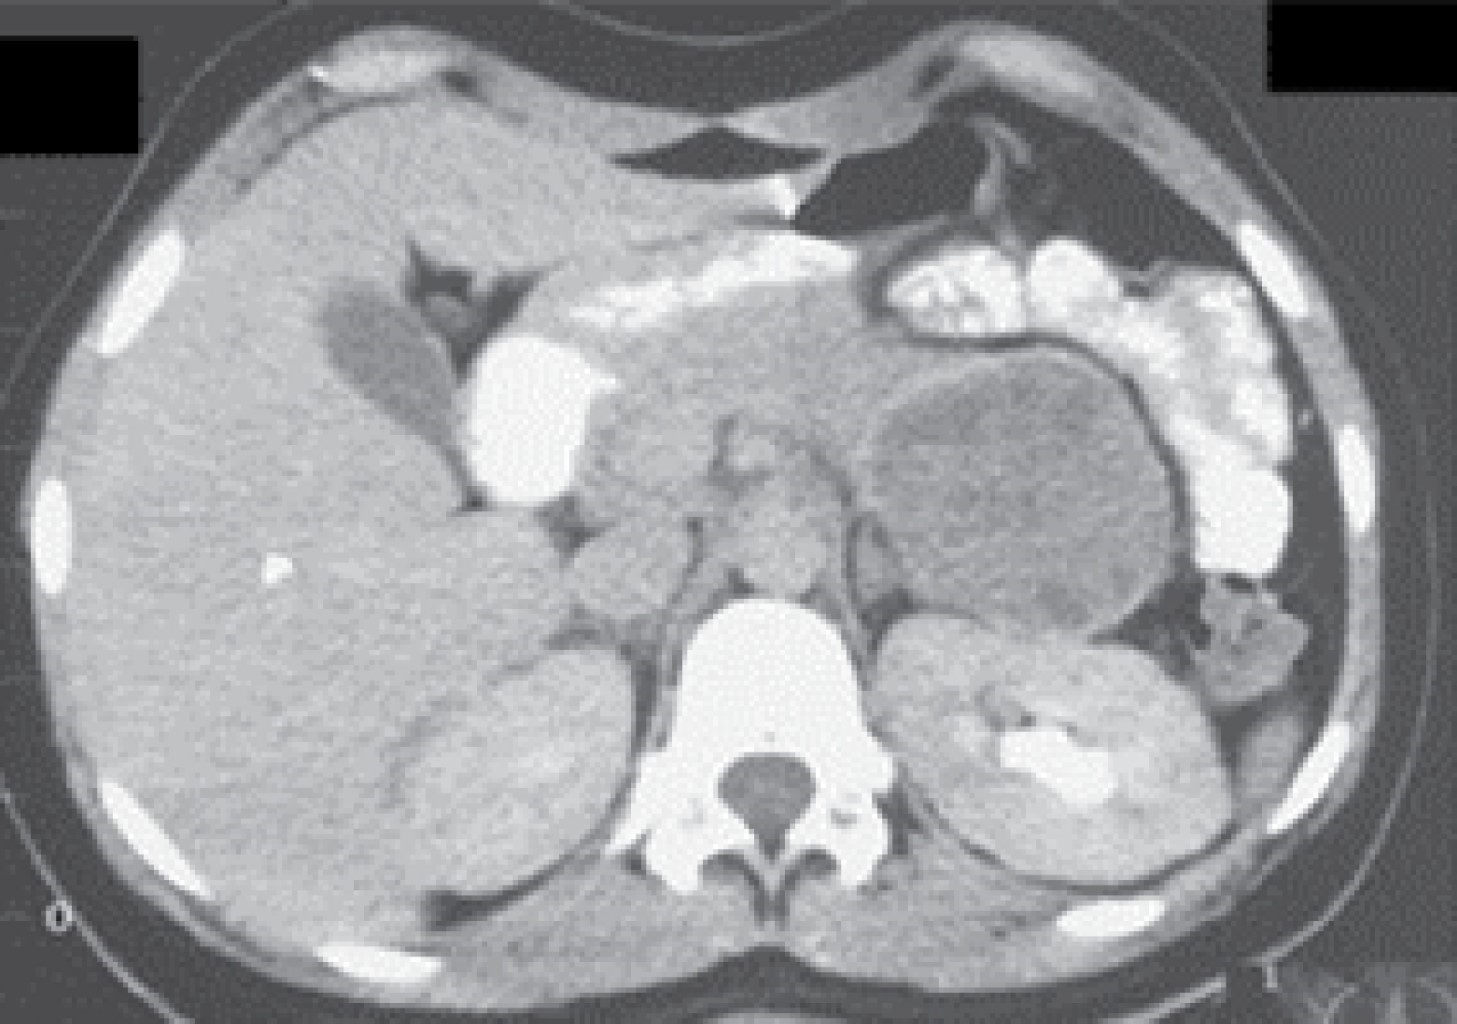

Computed axial tomography (CT) of the upper abdomen was performed with single and double contrast in axial sections, showing a pancreas with a severe increase in size in body and tail secondary to a large lesion of regular edges, with significant mass effect on retroperitoneal structures, isodense to the parenchyma, with hypodense areas not reinforced by intravenous contrast, without calcifications or cystic areas, measuring 102 × 107 × 115 mm (Figure 1), head and uncinate process without alterations, the rest of the study without alterations.

Laboratory and imaging paraclinical studies were performed, and blood laboratories (blood cytology, blood chemistry, liver function tests, PT, PTT, serum electrolytes, amylase, lipase) were found without alterations, as well as the chest X-ray; However, CT of the upper, lower abdomen and pelvic simple and with biphasic contrast not contrasted with diagnostic approach was requested, and as the only finding it was reported "spleen of normal size; however, there is a mass with 40 Hounsfield units with calcifications in the wall, well delimited, located in the splenic hilum measuring approximately 8.2 cm by 6.6 cm" (Figure 4). It was decided to perform surgery.

Computed tomography is the study of choice for the detection of pancreatic tumors; in Frantz's tumor, its most relevant tomographic features are an isolated location frequently in the head of the pancreas, a mixed location more frequently in the body and tail of the pancreas, predominantly solid content, mostly without calcifications, predominant size of 5-10 cm and mainly rounded shape with defined borders.10,11